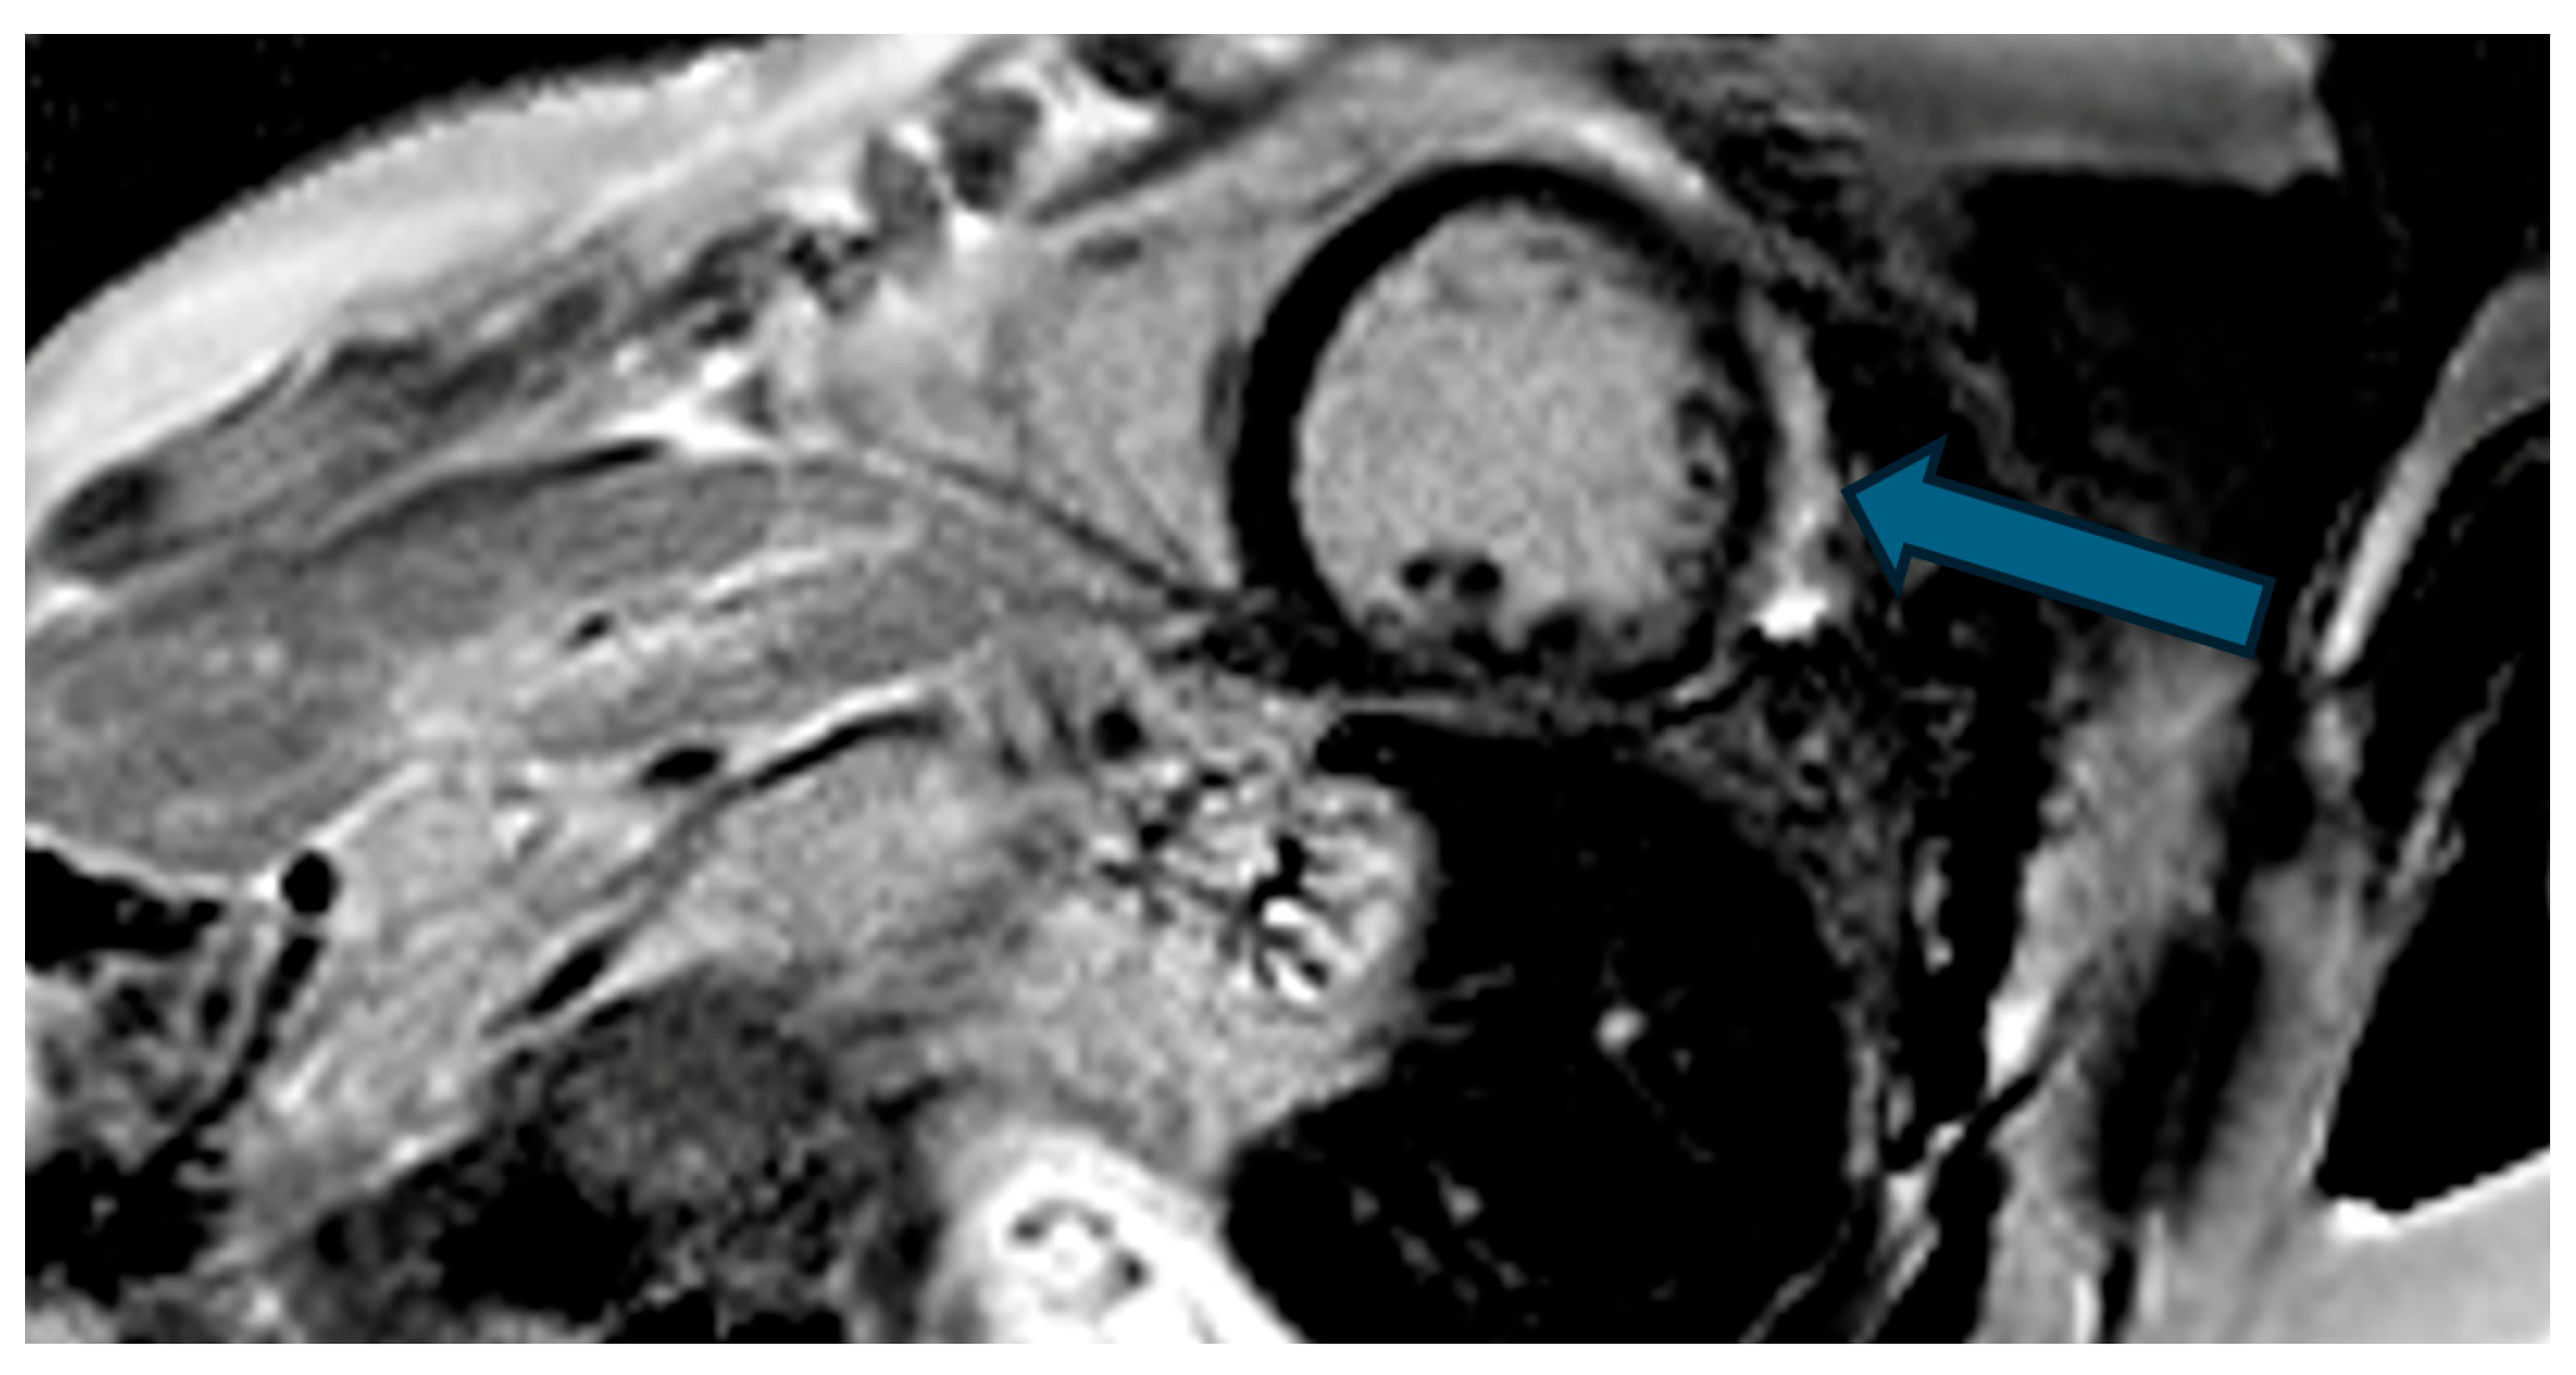

| Case | Patient (Sex, Age) | Symptoms | MAD (mm) | Valvular Issues | LGE | Other Details |

|---|---|---|---|---|---|---|

| 1 | Female, 61 years old | Syncope | 11 | MVP, mitral regurgitation | Lateral | Holter: atrial tachycardia and ventricular ectopy; cardiology follow-up planned for possible mitral valve repair |

| 2 | Male, 52 years old | Syncope and atypical chest pain | 10 | - | Lateral | History of ventricular arrhythmias; cardiology follow-up and Holter monitoring recommended |

| 3 | Female, 74 years old | Extrasystole | 3 | - | No LGE | No LGE; patient reassured and scheduled for periodic clinical follow-up |

| 4 | Male, 34 years old | Extrasystole in Marfan syndrome | 15 | MVP, valvular regurgitation | No LGE | Marfan syndrome; MVP with regurgitation; regular cardiology follow-up advised. |

| 5 | Male, 63 years old | Heart failure | 2,5 | MVP, valvular regurgitation | No LGE | Reduced LVEF (47%) with left atrial dilatation; heart failure therapy optimized; follow-up planned. |

| 6 | Male, 68 years old | Palpitations | 5 | - | Lateral | LGE in basal lateral wall; electrophysiological evaluation and ECG monitoring recommended. |

| 7 | Female, 53 years old | Extrasystole and syncope | 15 | MVP, valvular regurgitation | Basal-lateral | Extensive MAD with MVP and LGE; increased arrhythmic risk; antiarrhythmic therapy considered. |

| 8 | Female, 63 years old | Aortic and mitral regurgitation | 11 | Aortic and mitral regurgitation | Lateral | Aorto-mitral regurgitation with septal hypokinesia; mitral valve repair performed; heart failure therapy started. |

| 9 | Male, 45 years old | Palpitations and vertigo | 10 | - | Lateral | Basal lateral LGE; regular clinical and ECG follow-up recommended |